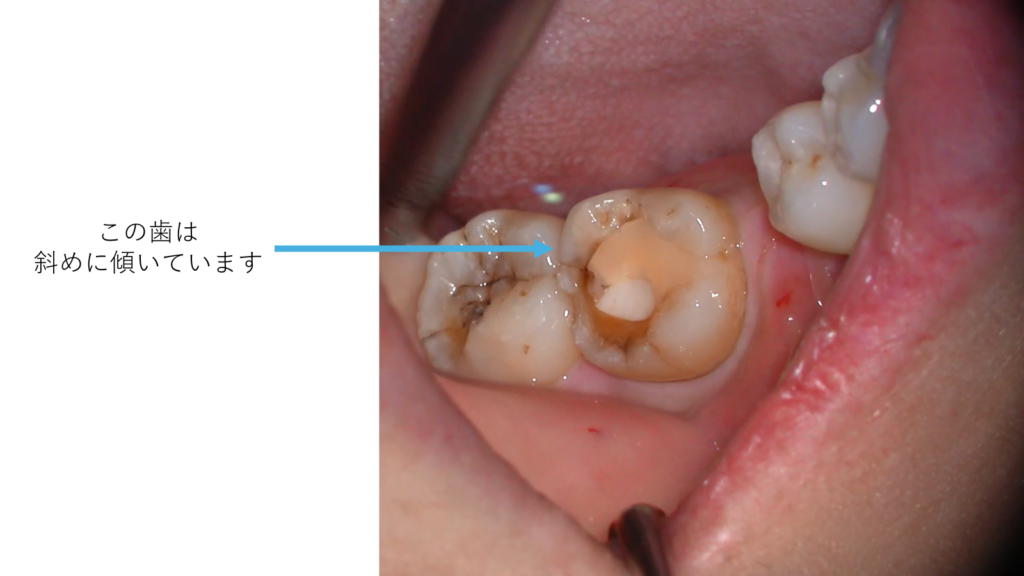

斜めに傾いた歯は、歯ぐきの奥に歯石が付きやすく、日々のブラッシングでは十分に届かないことがあります。その状態が続くと、歯周病のリスクは高まります。

矯正治療によって歯をまっすぐに整えることは、見た目の美しさを高めるだけでなく、清掃性を向上させ、歯を永く保つための予防医療でもあります。